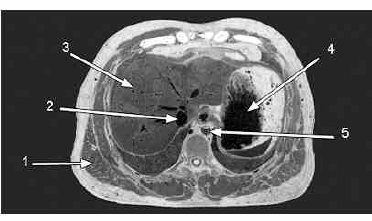

A figura acima mostra a fotografia de um corte anatômico realizado em cadáver. Considerando os dados mostrados na figura, julgue os itens a seguir.

A figura mostra um corte transversal, aproximadamente no nível da 11.ª vértebra torácica.